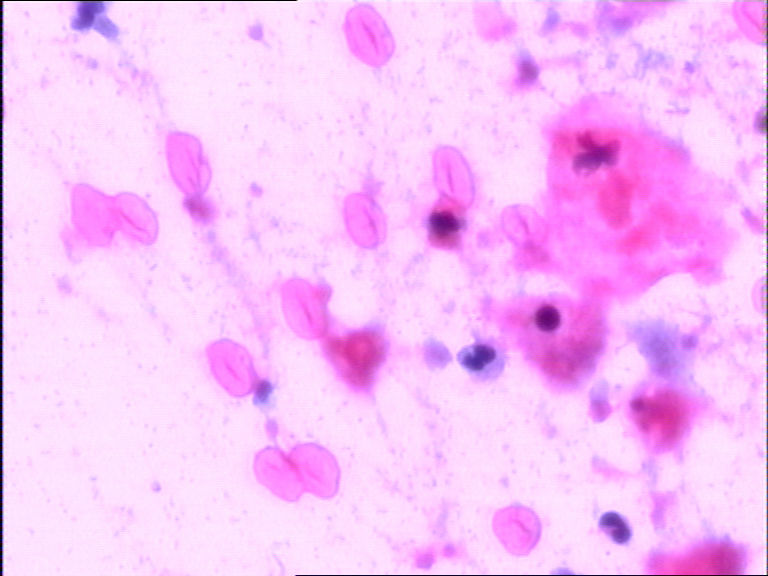

患者女38岁,宫颈TCT,巴氏染色。镜下有许多小细胞,胞膜较厚,胞浆较空,核呈长杆状。考虑是不是生物制品。求教各位老师。

• 宫颈TCT,未知细胞求解?图1

图1

感觉像未溶解的红细胞啊。

未溶解的红细胞

很好的一个病例,以前在纤支镜检中遇到过,抗酸染色出来很象结核。

花粉孢子

看大小形态是RBC

不知是否有滴虫.当然我说的滴虫不是楼主要关心的东东.楼主要关心的东东多半不是红细胞,是什么较难说,不除外结晶.

肯定不是红细胞,也不是未溶解的红细胞!是什么就有点不好说!

外用植物药后,残留植物成分。

我觉的是结晶的可能性比较大

开始几张看上去像红细胞

后2张看着像外来的什么,结合临床药史